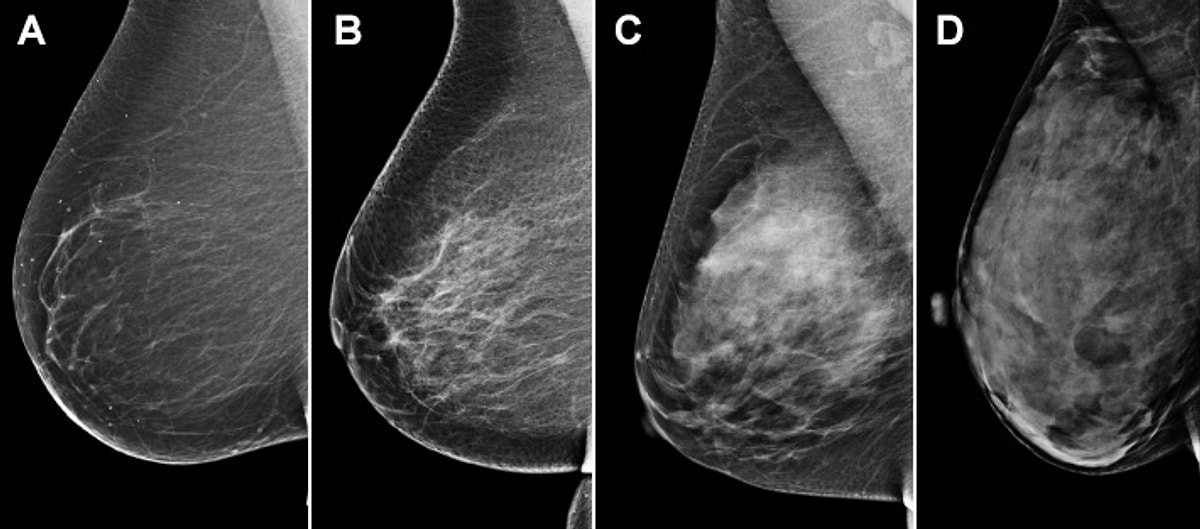

Birads 2 фкм 112 фотографий